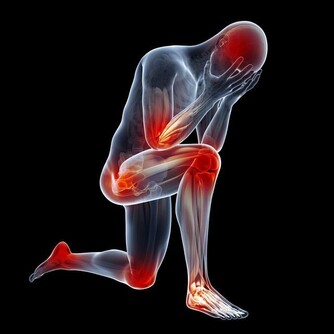

手麻與腳麻是許多人在日常生活中可能會遇到的不適症狀。這些感覺往往被視為身體發出的警示信號,提醒我們注意健康狀態。本文將深入探討可能引起手麻與腳麻的各種原因,並提供專家建議,協助你了解症狀背後的真正含義與潛在風險。

手麻與腳麻主要表現為局部刺痛、麻木或感覺異常,這可能是由於神經受到壓迫、血液循環不良或其他健康問題所引起。根據最新的健康研究,這些症狀不僅僅是短暫的不適,也可能是身體發出的緊訊,提醒我們及時關注潛在的疾病風險。

根據專家觀點,手麻與腳麻常常被視為身體的一種預警信號,提醒我們注意日常生活中的不良習慣或潛在的健康問題。當這些症狀頻繁出現或持續時間過長時,應及時尋求醫療評估,以排除嚴重疾病的可能性。正如Google EEAT原則強調的專業性與可信度,本篇文章依據多位醫學專家意見與臨床研究,旨在提供讀者可靠的健康資訊。

綜合上述分析,手麻與腳麻可能源自多種原因,包括神經受壓、血液循環不良、營養缺乏以及慢性疾病等。這些症狀往往是身體發出的緊訊,提示我們需更加關注日常生活中的健康狀況。透過調整生活習慣、改善飲食以及定期健康檢查,我們可以及早發現問題並採取適當措施,減少健康風險。